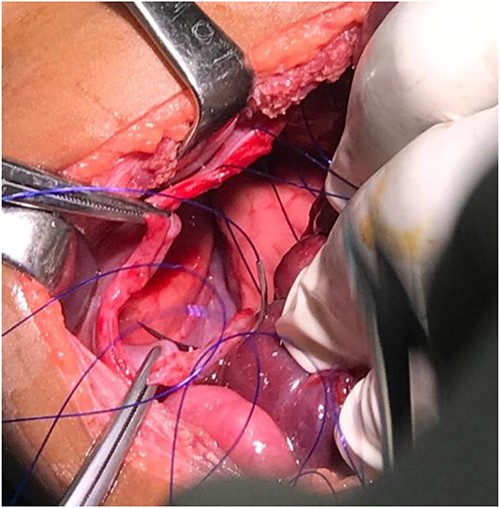

We performed exploratory laparotomy with Kocher incision 2 cm below the right costal margin abdomen opened by layers. The right lobe of the liver, transverse colon as well as part of small bowel were found herniating to the right hemithorax through a wide diaphragmatic defect around 10 cm in the greatest dimension, the liver was not injured but subcapsular haematoma of the right kidney. Thus, the hernia was reduced by gentle traction back of the right lobe of the liver and bowels to peritoneal cavity, exposing the right lung on the background. Furthermore, we visualized the right hemithorax through the bigger defect and found no signs of lung or large vessels injury or haemorrhage. 20Fr chest drainage in the right hemithorax was inserted to evacuate the pneumothorax and fluid collections. Thus, we repaired the defects with non-absorbable polypropylene suture (Prolene 2-0) in an interrupted fashion. No prosthetic mesh was used to cover the defects since the diaphragm did not show any sign of weakness. In the end, we achieved haemostasis. Later the patient was admitted to Paediatric ICU for close monitoring, intensive treatment and support. The post-operative rounds were regular and in day 7 postoperative, she was transferred back to paediatric surgery ward. After re-evaluations and lab values normalization, the patient was discharged day 16 postoperative (Figs 5-7).

Diaphragmatic defect well appreciable after abdominal viscera retraction.

Showing the non-absorbable polypropylene suture (Prolene 2-0) in simple interrupted pattern